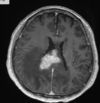

LINFOMA PRIMÁRIO DO SNC: 90% supratentoriais; Geralmente linfoma não hodgkin (celulas b); localização periventricular e nucleos da base; pode atravessar linha média (corpo caloso); TC: iso / hiperdensa com realce pos contraste; pode haver necrose; RM: Hipossinal em T1 e T2 com forte realce homogêneo pós contraste (realce anelar em imunossuprimidos); restrição a difusão;

127

Linfoma SNC Tumor infiltrativo, supratentorial, atravessa a linha média Acomete a profundidade dos hemisférios cerebrais Realce intenso sólido, sem necrose Restrição a difusão Hiposinal T2

Linfoma SNC